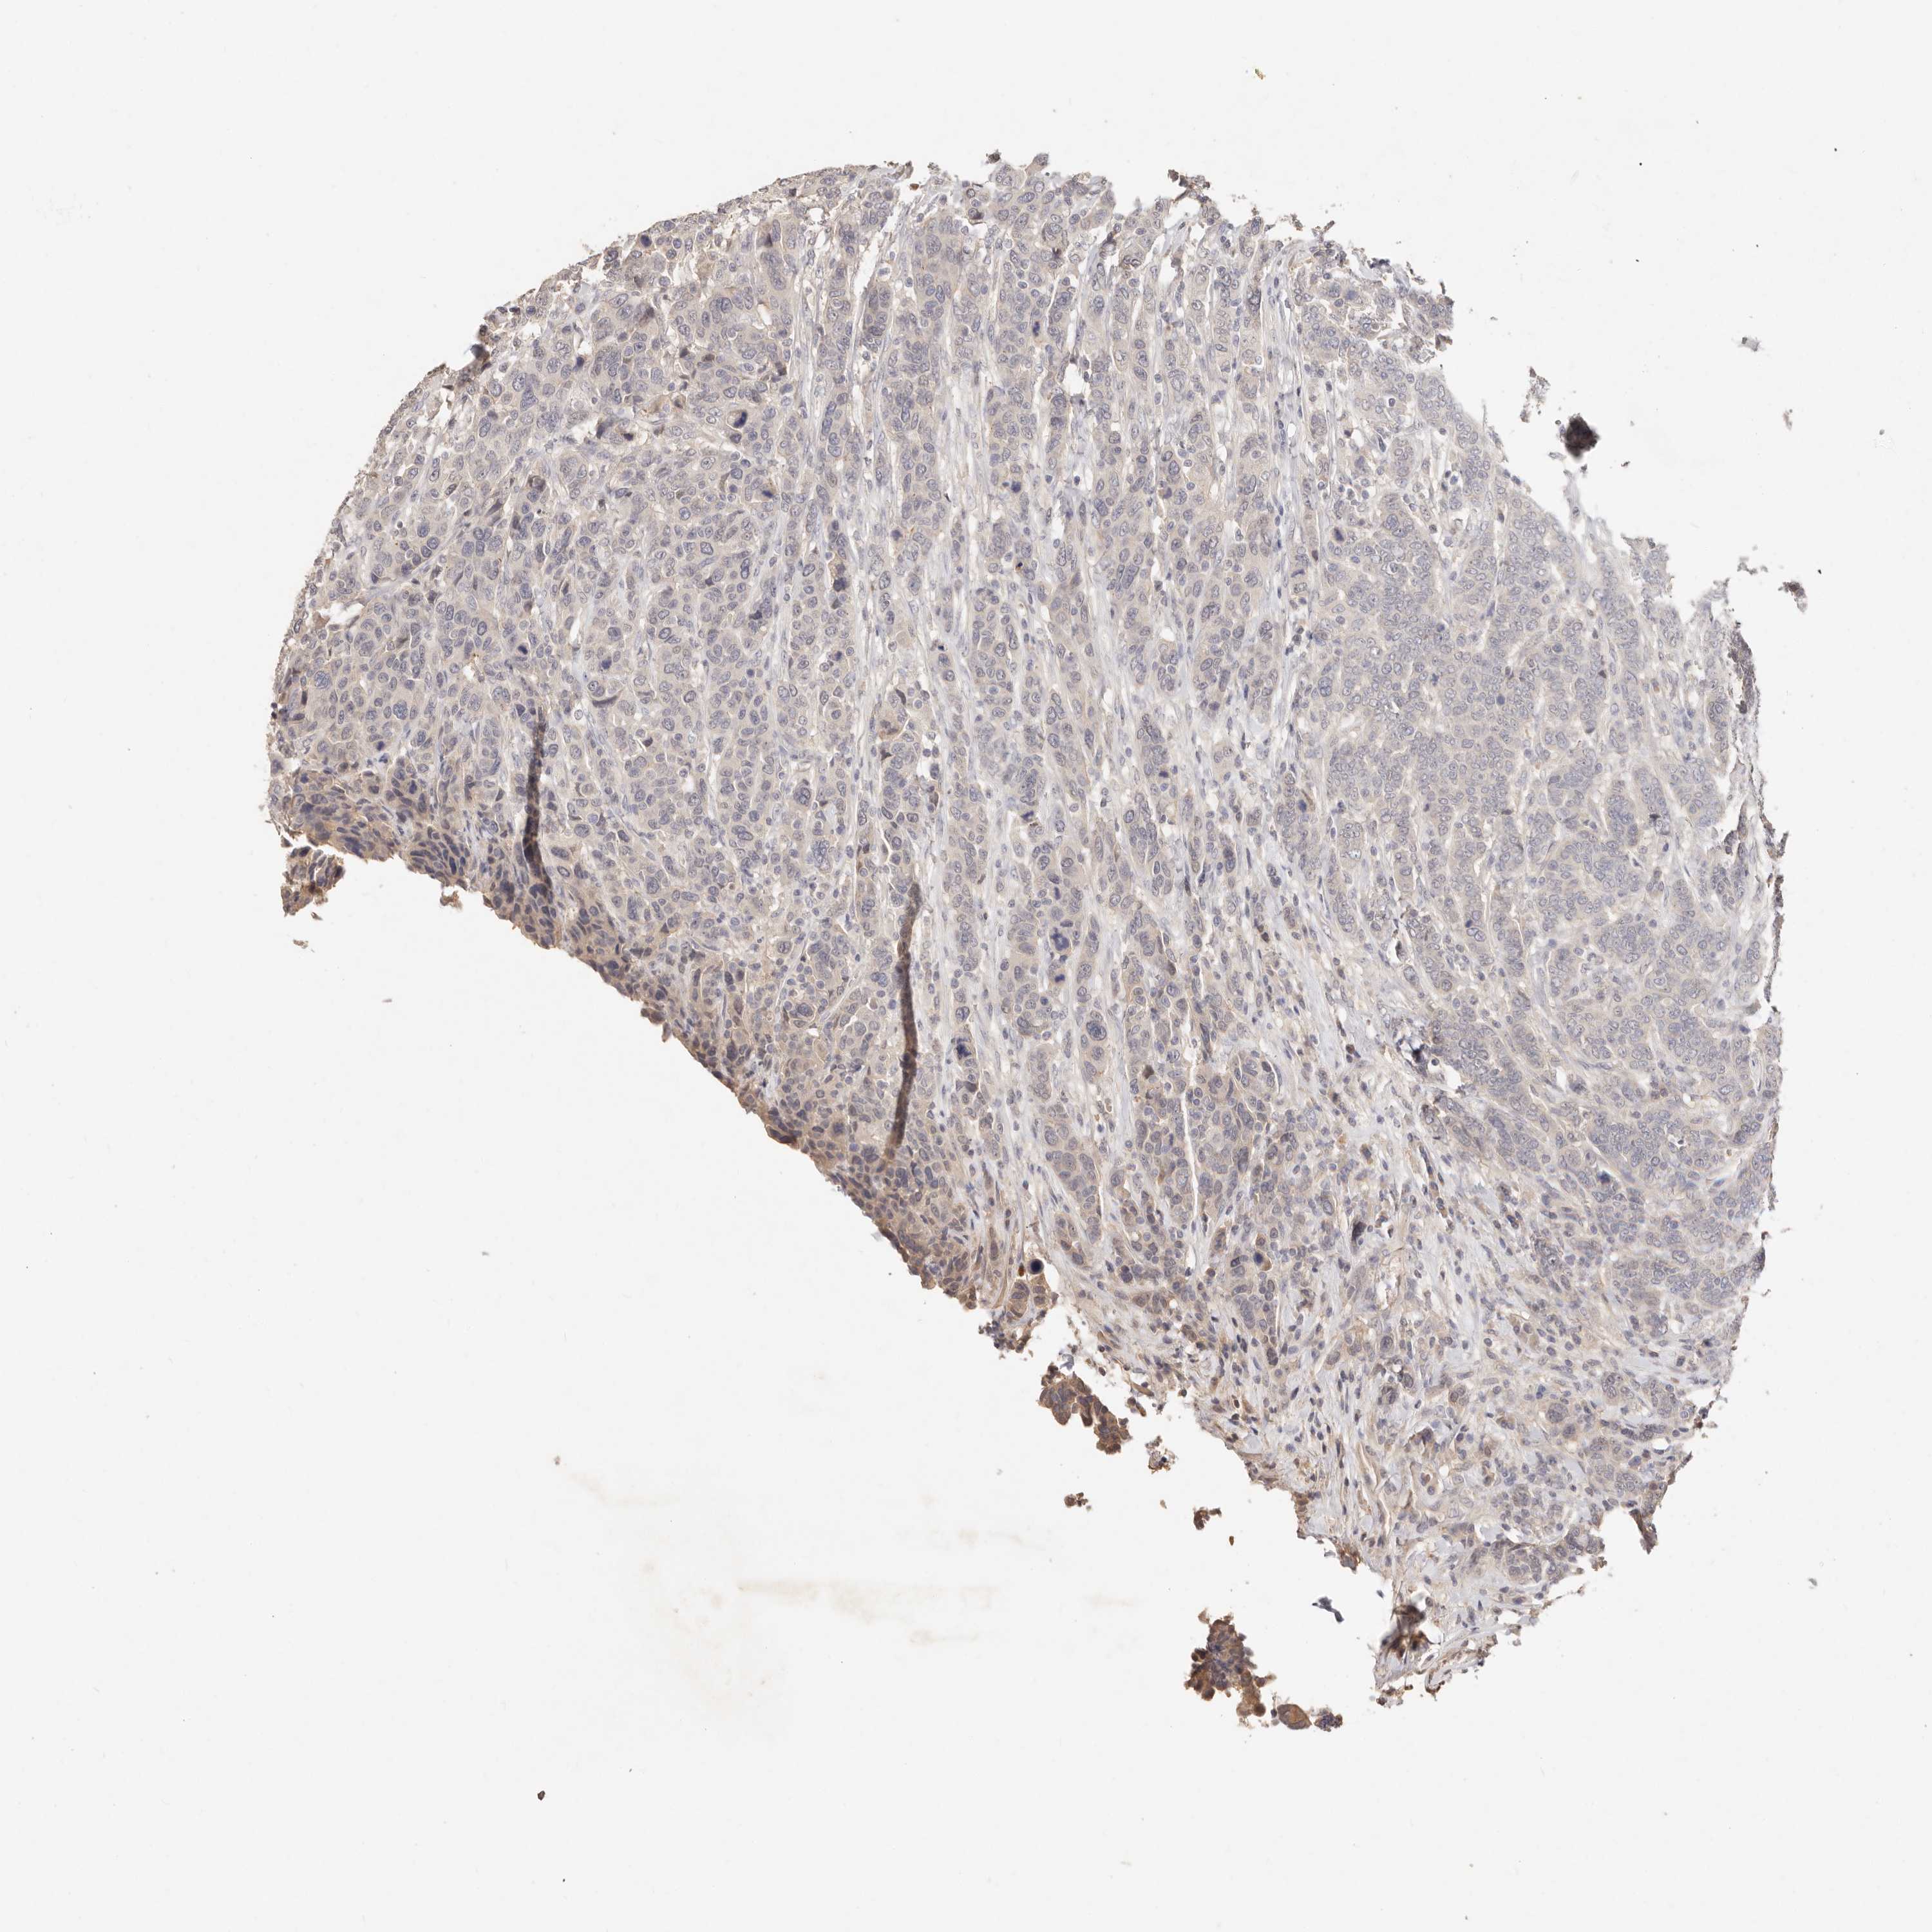

CANCER BREAST CANCER Show tissue menu

BRCA TCGA BRCA VALIDATION PROTEIN EXPRESSION